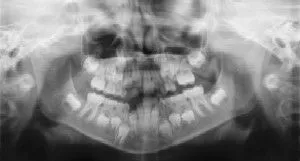

Dental Radiographs (X-Rays) - Pediatric Dentist in Ardmore, PA Radiographs (X-Rays) are a vital and necessary part of your child’s dental diagnostic process. Without them, certain dental conditions can and will be missed.

Radiographs detect much more than cavities. For example, radiographs may be needed to survey erupting teeth, diagnose bone diseases, evaluate the results of an injury, or plan orthodontic treatment. Radiographs allow dentists to diagnose and treat health conditions that cannot be detected during a clinical examination. If dental problems are found and treated early, dental care is more comfortable for your child and more affordable for you.

The American Academy of Pediatric Dentistry recommends radiographs and examinations every six months for children with a high risk of tooth decay. On average, most pediatric dentists request radiographs approximately once a year. Approximately every 3 years, it is a good idea to obtain a complete set of radiographs, either a panoramic and bitewings or periapicals and bitewings.

Pediatric dentists are particularly careful to minimize the exposure of their patients to radiation. With contemporary safeguards, the amount of radiation received in a dental X-ray examination is extremely small. The risk is negligible. In fact, the dental radiographs represent a far smaller risk than an undetected and untreated dental problem. Lead body aprons and shields will protect your child. Today’s equipment filters out unnecessary x-rays and restricts the x-ray beam to the area of interest. High-speed film and proper shielding assure that your child receives a minimal amount of radiation exposure.